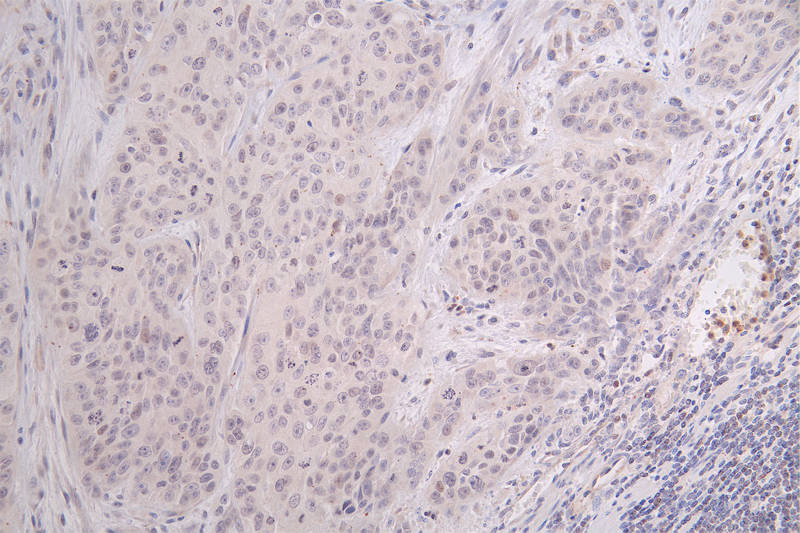

IHC image of CSB-RA148519A0HU diluted at 1:100 and staining in paraffin-embedded human breast cancer performed on a Leica BondTM system. After dewaxing and hydration, antigen retrieval was mediated by high pressure in a citrate buffer (pH 6.0). Section was blocked with 10% normal goat serum 30min at RT. Then primary antibody (1% BSA) was incubated at 4°C overnight. The primary is detected by a Goat anti-rabbit polymer IgG labeled by HRP and visualized using 0.09% DAB.